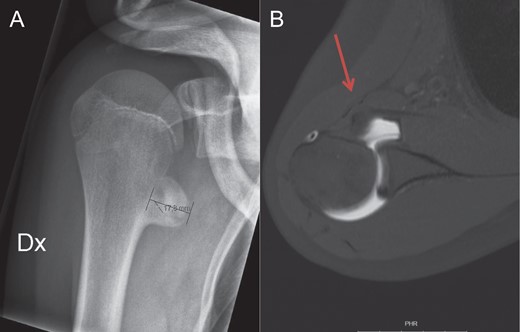

Axillary lateral view of the injured right shoulder. The avulsion fragment of the lesser tuberosity is marked by the red arrow.